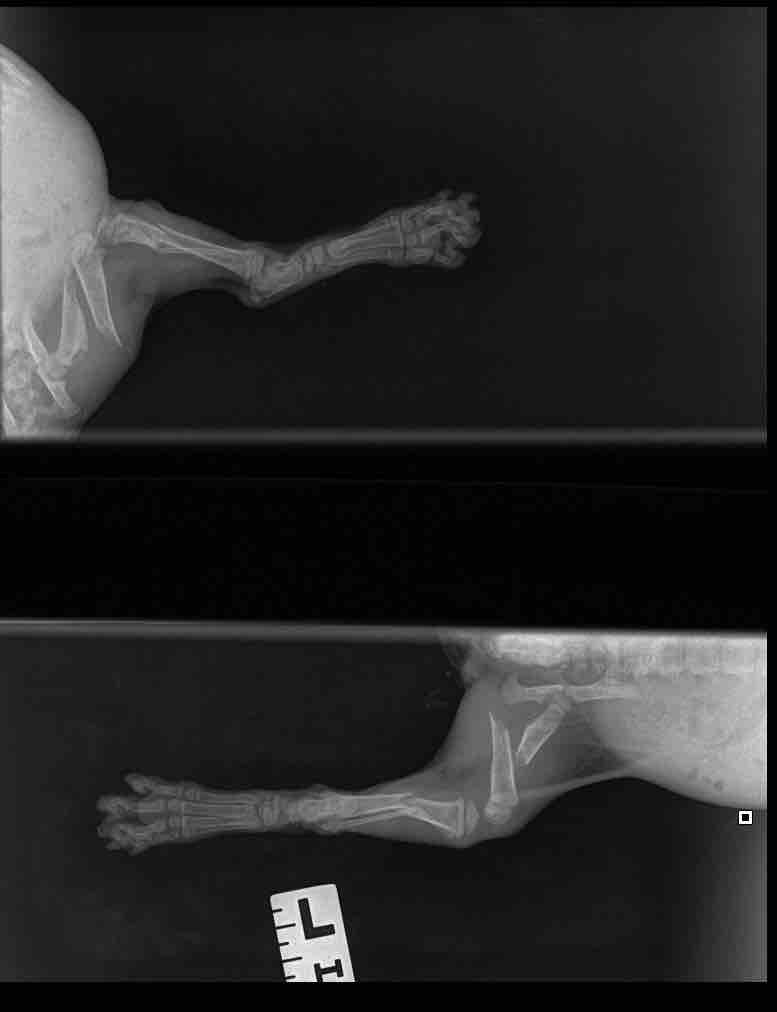

Hey everyone! I’ve created a GoFundMe page to help raise money for Sugar and Sophia. Sugar is my latest rescue. She was found on the streets with her sister and was injured. After a few vet visits, the vet confirmed it was a double fracture and needed surgery ASAP before it gets worse than it already is. The surgery will most likely be done by the 3rd of Jan latest. I’ve included the minimum estimation for the surgery which is 1,932 USD (584.40 KWD).